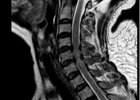

近日,省人民医院帮扶专家和我院骨科团队为一位颈脊髓损伤、四肢不全瘫的患者进行手术治疗,术后患者四肢肌力恢复正常,家属连连感谢和赞叹。57岁的李阿姨不慎从山上摔下2023-06-29